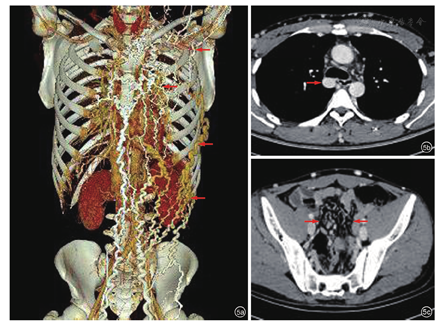

肝脏超声未见异常。胸部增强CT检查提示:右侧锁骨下静脉,上腔静脉均未显示,考虑闭塞。胸壁静脉扩张强化明显,右侧奇静脉扩张代偿。前纵膈高密度影,胸腺退化不全可能性大(图2a,图2b)。

胸腹部增强CT检查(2019-4-17):(1)可见颈部与胸部浅静迂曲、扩张代偿(图5a);(2)可见代偿扩张粗大的奇静脉(图5b);(3)盆腔静脉丛迂曲、扩张(图5c)。根据患者体征及相关检查我们绘制了该患者静脉侧支回流路径模式图(图6),供临床参考。